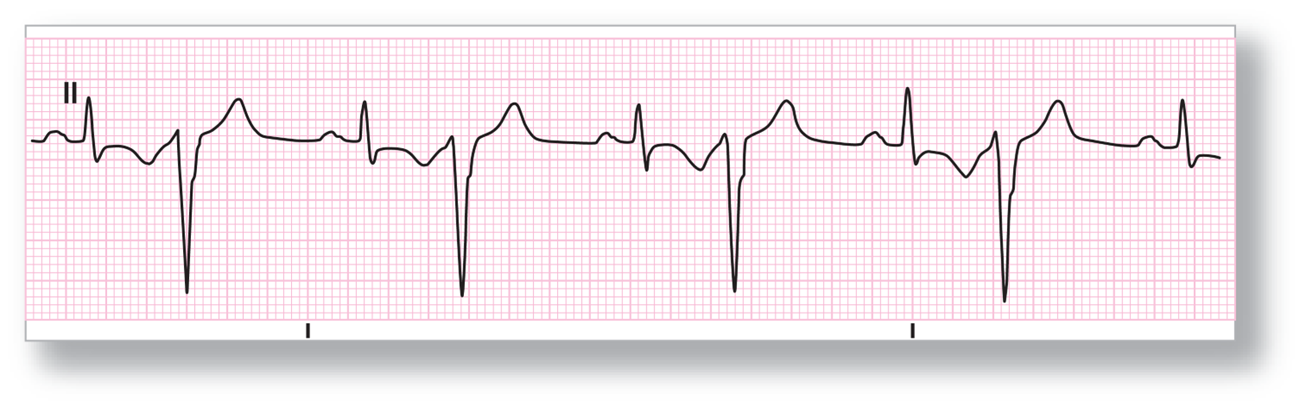

Premature ventricular complex (PVC)

§Unifocal premature ventricular complexes

Premature ventricular complex- Multifocal

Premature ventricular complex

Couplet

Bigeminy, Trigemini